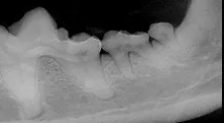

Kyle Animal Hospital is on Jack Hays Trail, just across from the Plum Creek subdivision in Kyle. We have a fully-equipped pharmacy, lab, ultrasound, dedicated dental room and surgery suite. With upgraded diagnostic equipment, Kyle Animal Hospital has one of the best equipped in-house laboratories in the area. Our radiology facilities offer the latest in high-frequency digital technology. Inpatient facilities include boarding and hospitalization.

- Radiology services

- Dental services